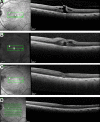

Purpose: This work aims to evaluate the outcomes of a series of macular hole (MH) surgical procedures in patients who had pars plana vitrectomy (PPV) with internal limiting membrane (ILM) peel and without gas tamponade.

Methods: Patients from a retina specialty clinic who had MHs were identified for this interventional case series. Patients with small MHs were offered inclusion into the trial. Patients with larger MHs were excluded. They underwent standard 3-port PPV and ILM peel without gas or air to treat small MHs. The main outcomes that we measured were closure of MH and visual results.

Results: Small MHs in 5 patients were managed with PPV and ILM peel alone. The average preoperative hole size at its narrowest width was 227 µm (range, 173-294 µm). Four of 5 patients (80%) had successful hole closure without a gas tamponade and improved vision; 1 patient did not have hole closure and was treated with an in-office gas bubble to close the hole. The average preoperative vision at 3 months was 20/80- (54 Early Treatment Diabetic Retinopathy Study [ETDRS] letters) and improved to 20/30-2 (73 ETDRS letters) in the 4 patients whose MHs were closed with surgery without a gas bubble. This was statistically significant (P = .003). The hole that did not close initially without gas tamponade was the largest in the series.

Conclusions: Patients with small MHs can be successfully treated with a vitrectomy and ILM peel alone without a gas tamponade.